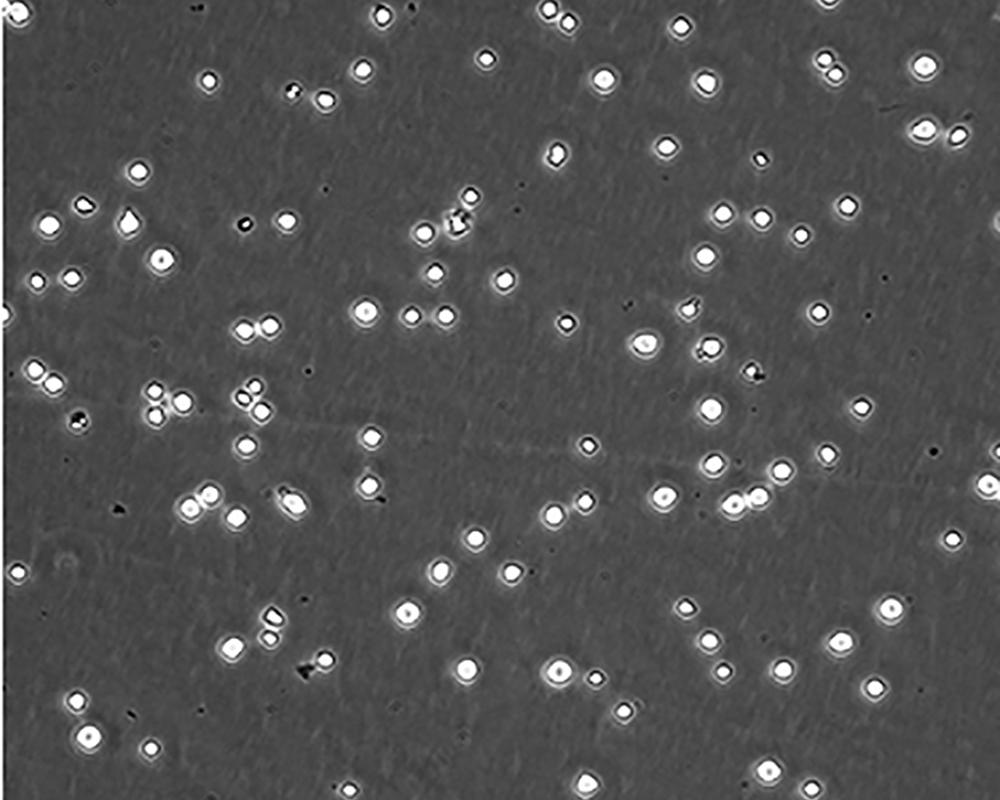

生長特性 suspension

形態特征 lymphoblast

細胞描述 CEM/C1是人T細胞白血病細胞株CCRF-CEM(見ATCC CCL-119)具有喜樹堿抗性的衍生株。1991年細胞株選擇并亞克隆了對CPT的抗性。細胞表現出對CPT類似物水溶性的托泊替康和非水溶性的9-氨基-CPT及10,11-亞甲二氧基-CPT具有交叉抗性。CEM/C1細胞對CPT的敏感性較母系CEM細胞低31倍。CEM/C1細胞表現非典型的多藥抗性和轉換拓補異構酶I催化活性。對CPT的抗性維持6個月以上。